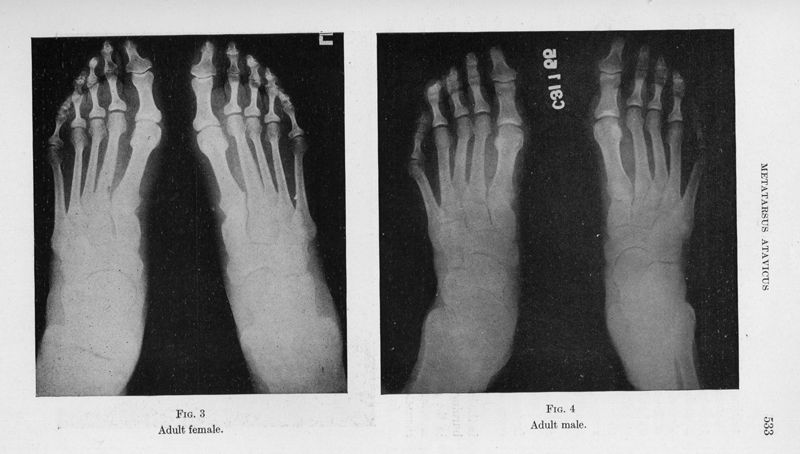

Metatarsus atavicus. The identification of a distinctive type of foot disorder

In : [The] Journal of bone and joint surgery, 1927, Vol. 9, pp. 531-44